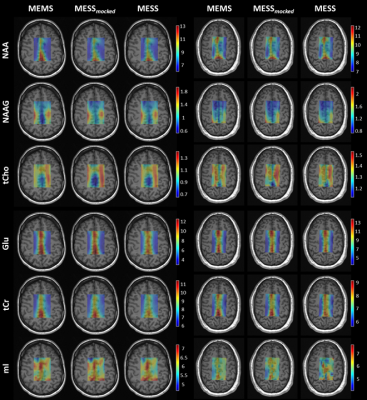

A comparison of concentration and T2 maps across two volunteers is reported in Fig.3 and Fig.4 for a subset of metabolites. MESS-mocked replicates MEMS adequately, thus signal truncation is found suitable for concentration and T2 mapping. MESS yields maps that overall agree with the 3-fold slower MEMS technique here considered the gold standard for comparison. The distribution of concentrations and T2s between GM and WM is reported in general agreement with the literature.13,15–19

Fig.3: Concentration maps in milli-molar units [mM] for a subset of metabolites displayed for two subjects and the three methods (MEMS, MESS-mocked, and MESS). NAA: N-acetylaspartate, NAAG: N-acetylaspartylglutamate, tCho: total choline, Glu: glutamate, tCr: total creatine, and mI: myo-inositol. Maps are displayed with zero-filling in spatial domain with cropped voxels at the edges (20x20 voxels).